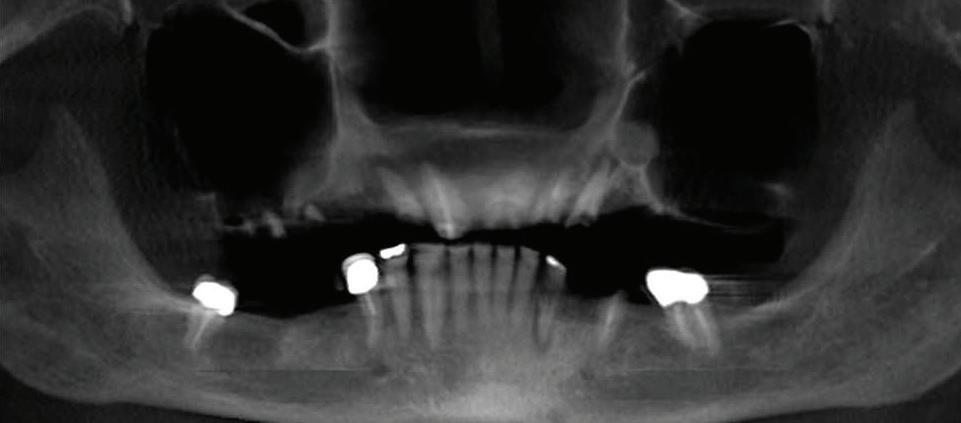

Can just four implants replace all of the teeth on the top or the bottom of your mouth? Thanks to advances in dental implant technology, that answer is a resounding yes.

Believe it or not, tooth loss is extremely common among adults, especially as we age. In fact, more than 35 million people in America are missing

all of their upper and/or lower teeth. Rather than living with the discomfort and hassles of dentures, many people are opting for what is called “all-onfour” dental implant restoration.

All-On-Four: One Full Arch Of Teeth, Four Dental Implants

To fully understand this remarkable technique for replacing teeth, you should first understand what a dental implant is. An implant is a small titanium screw that fits inside your jawbone and replaces the root-part of a missing tooth. Minor surgery is required to insert the implants. Once the implant is in place, a crown is attached to give you a highly realistic-looking and functional prosthetic tooth. Here’s where it gets really interesting: You do not need a dental implant for each and every one of your missing teeth. All you need is four

Please see “All-On-Four,” page 38